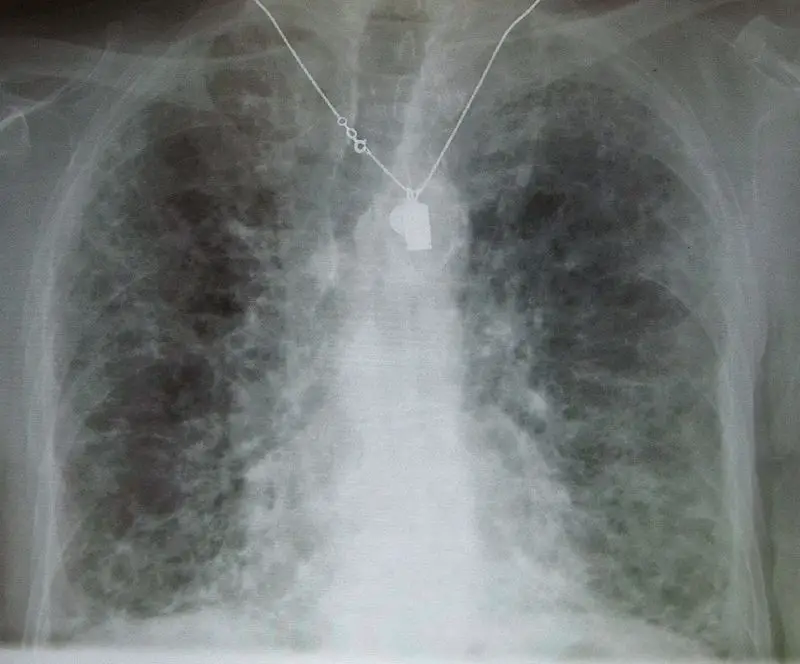

Three common patterns of pneumonia may be detected on chest X-ray which include:

- Interstitial pneumonia

Interstitial Pneumonia

Interstitial pneumonia is also known as atypical pneumonia.

Diffuse interstitial infiltrates are the defining features of interstitial pneumonia.

Interstitial pneumonia presents with only a few minor upper respiratory symptoms (low fever, little sputum) which is an ‘atypical’ presentation.

Interstitial pneumonia is typically caused by bacteria or viruses.